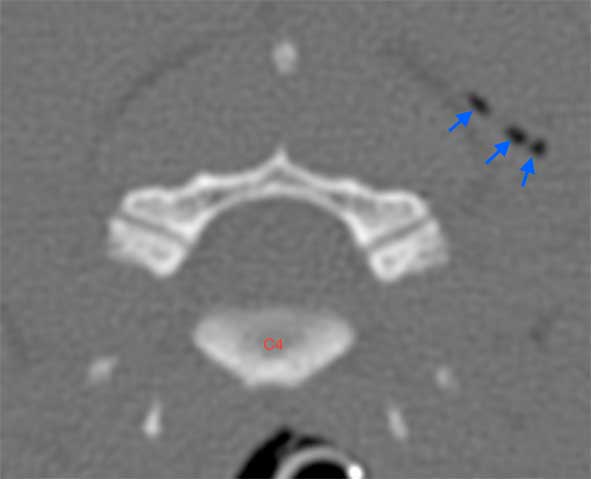

CT was performed and showed a metal artifact typically displayed as bright and dark streaks at the level of the right dorsal lamina of the C4. This was associated with a small defect within a right lateral cutaneous and SC tissues, and several small gas attenuating foci throughout the soft tissues at this level. These findings supported a penetrating neck injury (Figure 2).

The metal artifact prevented the assessment of any injuries affecting the cervical vertebrae, so Lucy underwent a surgical intervention to remove the bullet.